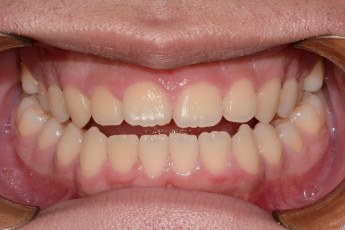

Before

After